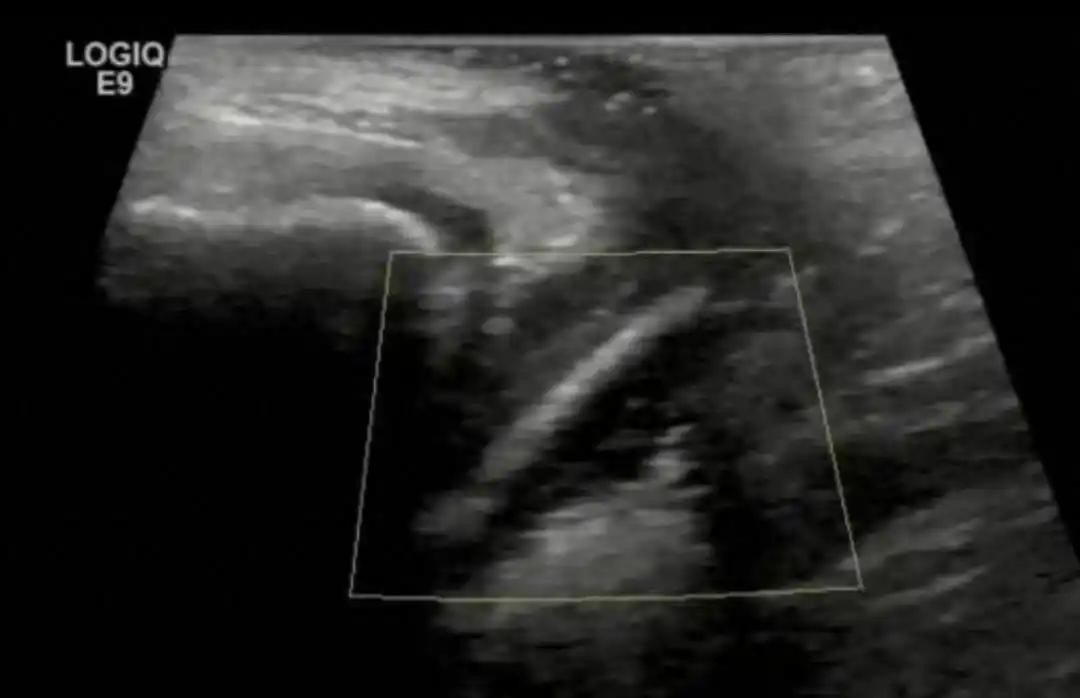

万万没想到!广东惠州,一名7岁女孩下体不舒服,妈妈一开始还没重视,以为抹抹药就好了,可孩子反复阴道炎,让妈妈察觉到不对劲,带着她去深圳检查,医生竟从孩子体内取出完整的试用装精华液 起初,妈妈想着小孩子嘛,可能是不注意卫生,或者天气热捂着了,给抹点药膏应该就能好。但问题是,反反复复就是好不了 药也吃了,洗液也用了,外用的药膏也换了好几种,折腾了好几个月,孩子的症状始终没有彻底消失,妈妈这才真正警觉起来,觉得事情没那么简单 到了医院,医生听完病史后,很快判断这不像普通的感染。普通阴道炎,规范用药之后一般都会好转,拖了几个月还不好,背后很可能有别的原因 医生建议做个超声检查。结果一出来,真相大白,阴道内有异物 也就是说,有个不该出现在那里的东西,一直卡在孩子体内,反复刺激黏膜,引发感染,这才导致阴道炎反反复复不好 问题找到了,但新的问题来了:是什么东西?怎么进去的? 医生没有直接下结论,而是很耐心、很温柔地和小女孩单独聊了聊。孩子最终说了一句让妈妈当场愣住的话:一个月前,她往身体里塞了一个东西,大概圆珠笔那么粗 后来医生发现,卡在孩子阴道里的,竟然是一整支试用装精华液,最后顺利取出,孩子的炎症就好了 有网友说:小孩子好奇,喜欢往有洞的地方塞东西,很正常啊,我小时候还在鼻子里塞了一颗豆子,费了好大劲才弄出来 确实如此,孩子的想法和成年人不同,耳朵、鼻孔、尿道,都可能有孩子塞进去的各种小东西,豆子、珠子、电池、笔帽、棉花、玩具零件 尤其是学龄前和低年级的孩子,对自己身体的孔洞有天然的好奇心,这是他们探索世界的一种方式,不是什么特别异常的行为 这个7岁的小女孩最终没事了,东西取出来了,炎症也消了。但每次看到这样的案例,都觉得孩子能说出来、医生能想到、家长能坚持,这三样缺了哪一个,结果都可能完全不同 希望这个事能给更多人提个醒:孩子的身体不会说谎,反反复复好不了的毛病,背后一定有原因。找对了,可能就是一条明路